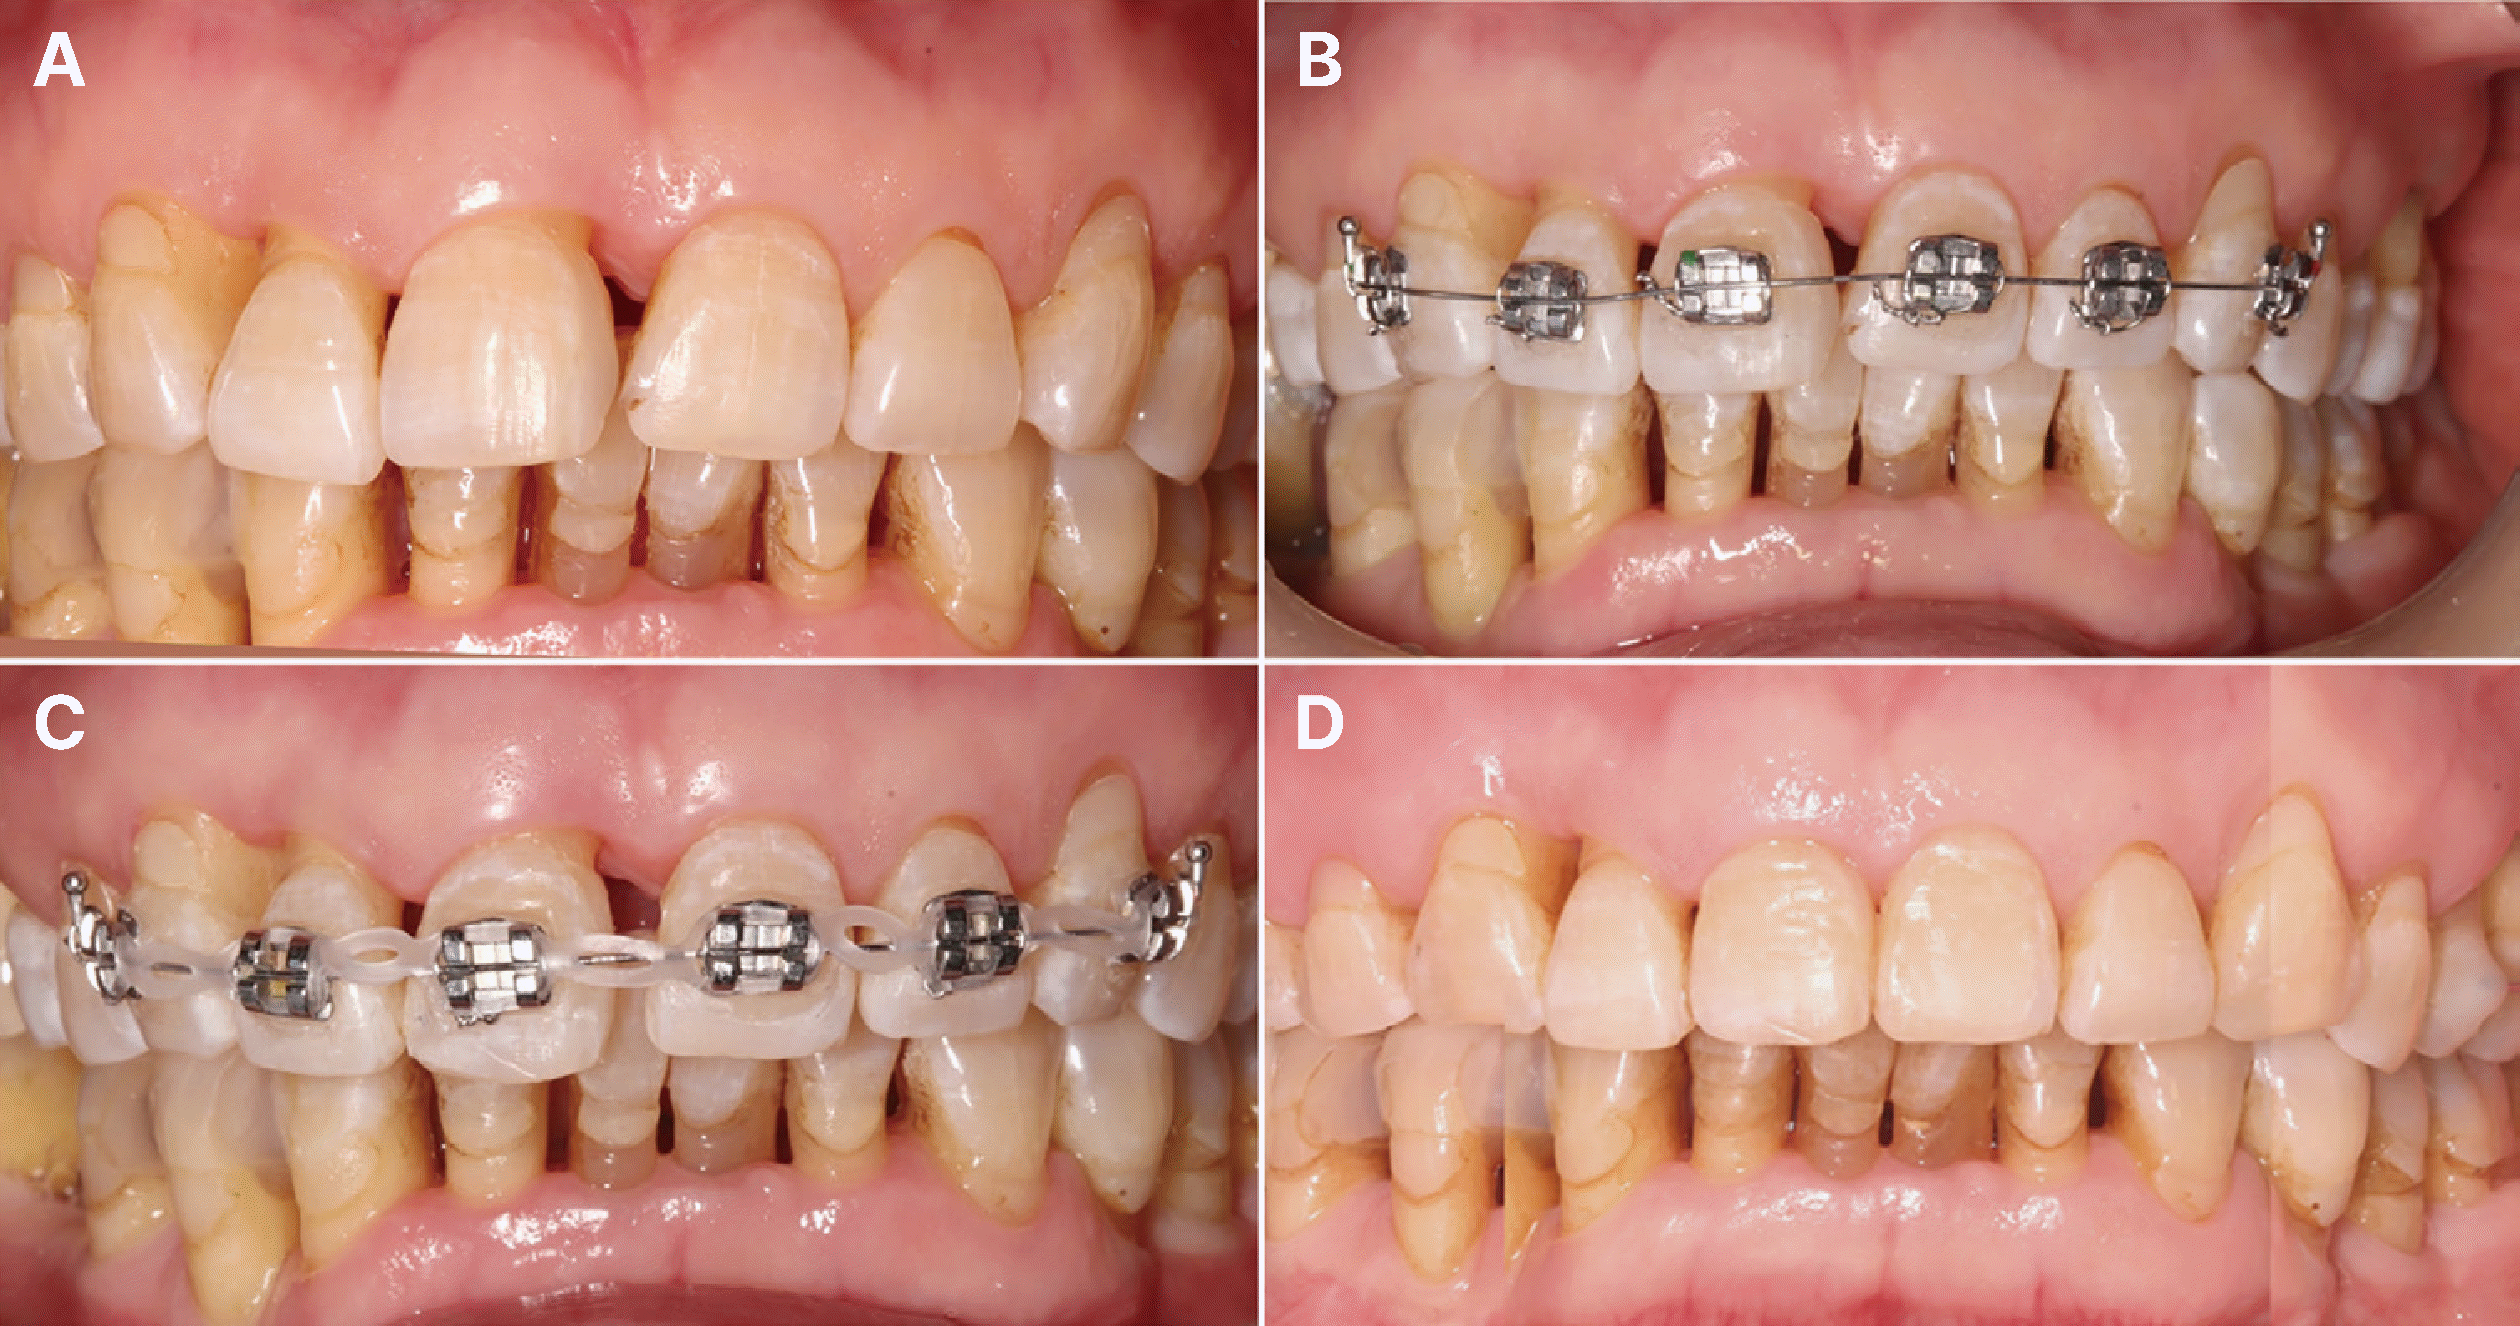

Fig. 3

Panoramic radiographs of Case 2: preoperative (A) and post-periodontal and orthodontic treatment (B). Severe intrabony defects involving multiple teeth were transformed into a flat bone morphology following successful periodontal therapy. Note the significant bone gain on the mesial aspect of the right maxillary central incisor, attributed to the synergistic effect of periodontal and orthodontic treatment (B).